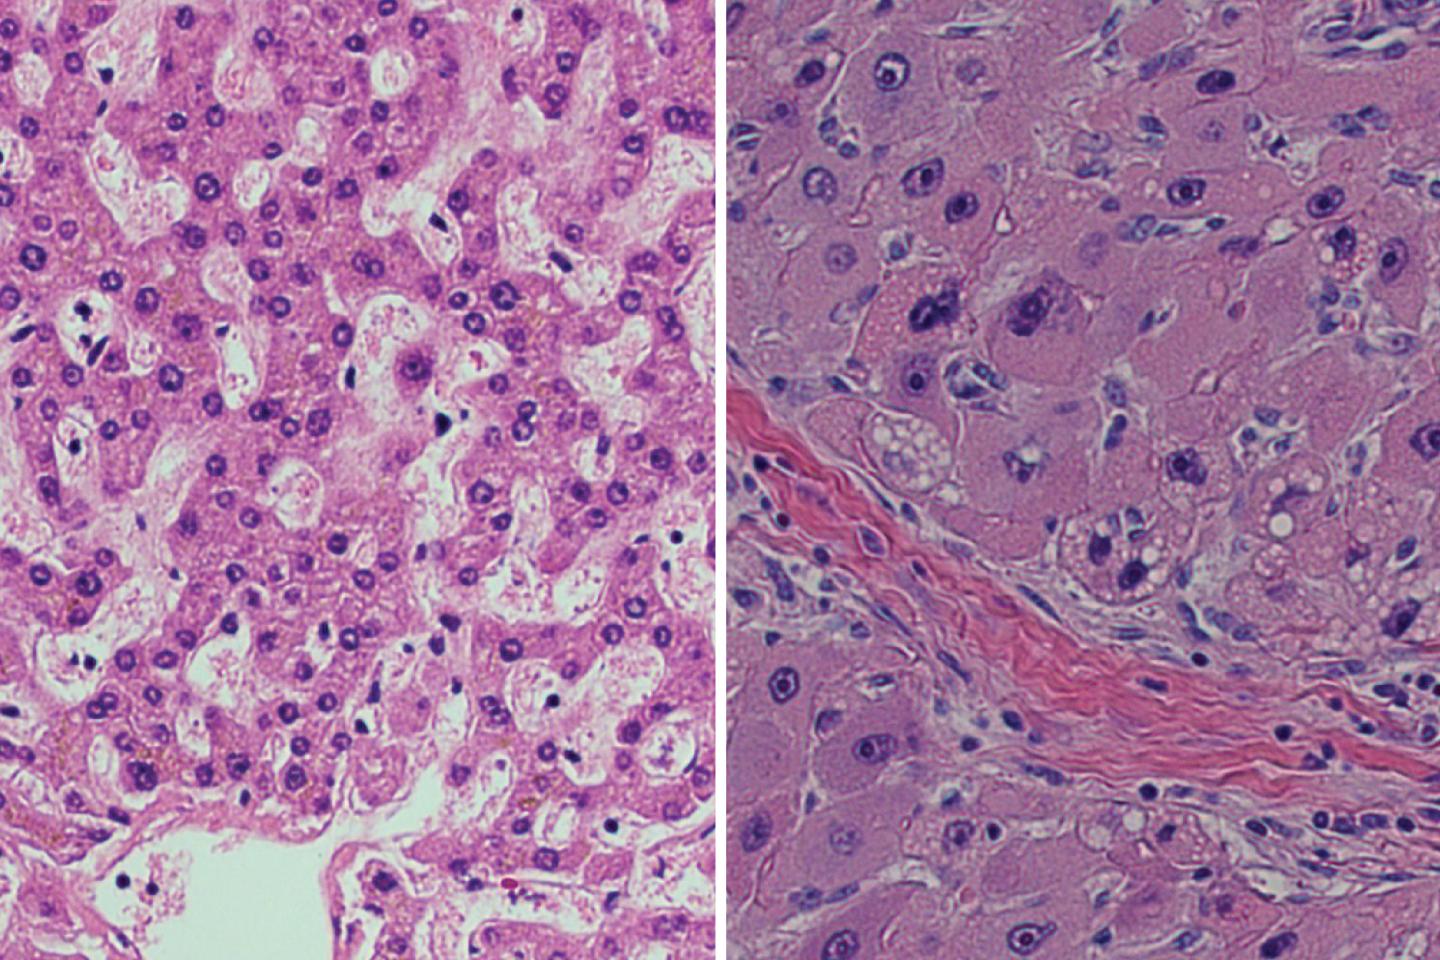

After years of rigorous research, a team of scientists has identified the genetic engine that drives a rare form of liver cancer. The findings offer prime targets for drugs to treat the usually lethal disease, fibrolamellar hepatocellular carcinoma (FL-HCC), which mainly strikes adolescents and young adults.

In work published this week in the Proceedings of the National Academy of Sciences , the scientists used CRISPR gene editing, a highly precise tool for manipulating DNA, to generate mice that carry the 400,000 base-pair deletion and produce the chimeric gene. Edward Kastenhuber, a graduate student in Lowe's lab, found that these mice develop liver tumors that mimic the biology of the tumors found in humans with FL-HCC, suggesting that the deletion is in itself sufficient to cause the cancer--other alterations are not necessary for tumors to grow.